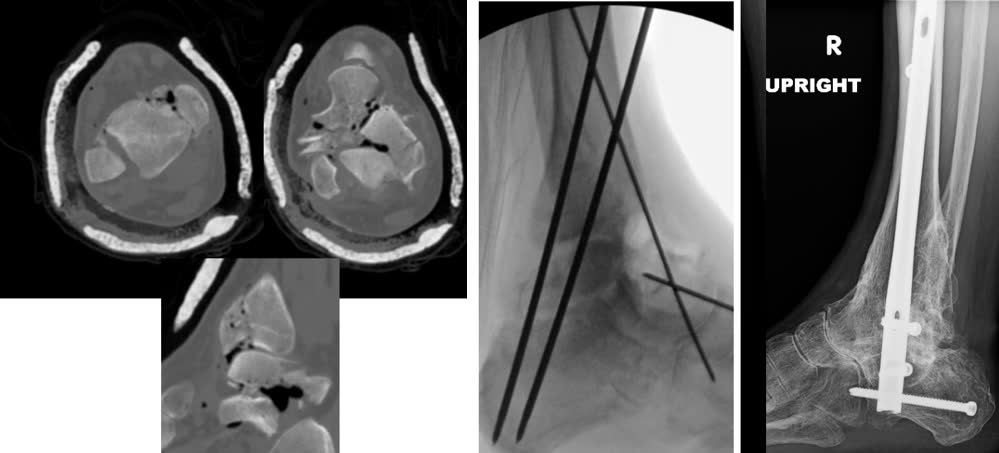

Визуализация

Рентгенография

Стандартные проекции: передне-задняя, боковая, проекция Mortise — для первичной оценки типа перелома и смещения.

КТ с 3D-реконструкцией

КТ является обязательным исследованием при всех переломах пилона [Flores et al., OTA Int, 2023].

Протокол:

- Аксиальные срезы ≤1 мм через дистальный отдел большеберцовой кости (10–15 см проксимальнее плафона)

- Сагиттальные и коронарные реконструкции

- 3D-реконструкция с субтракцией малоберцовой кости

Задачи предоперационного планирования по КТ:

- Определение паттерна повреждения колонн

- Оценка зон импакции суставной поверхности

- Картирование линий перелома на аксиальных срезах для планирования доступов

- Оценка перелома малоберцовой кости (простой vs сегментарный — сегментарный является маркером повреждения синдесмоза и худших исходов) [Purcell et al., J Orthop Trauma, 2022]

- Поиск ущемления сухожилий (задняя большеберцовая мышца) — частота описана в комбинированных сериях [Sousa et al., 2023]

- Оценка повреждения синдесмоза (25% случаев) [Christensen et al., 2022]

Этапный протокол (золотой стандарт)

Этапное лечение (протокол Sirkin) остаётся золотым стандартом при переломах пилона с повреждением мягких тканей.

Этап 1 (день 0–1):

- Временная чрескостная фиксация аппаратом внешней фиксации (АВФ) — дельта-рама или блокирующая конструкция через голеностопный сустав (возможно также использование классических конструкций)

- Репозиция малоберцовой кости и остеосинтез

- Обработка раны при открытом переломе

- Опционально: ограниченная репозиция и фиксация большеберцовой кости (LTRF — Limited Tibial Reduction and Fixation) при первичной операции

Этап 2 (день 10–21, при адекватном состоянии мягких тканей):

- Окончательный остеосинтез через соответствующий доступ на основании данных КТ

- Тест «морщин» (wrinkle test) — появление складок кожи свидетельствует о готовности мягких тканей к операции

Сроки: среднее время между этапами при стандартном протоколе 15,61 ± 8,59 дней. При выполнении LTRF на первом этапе время сокращается до 10,86 ± 7,44 дней (на 4,75 дня быстрее, P=0,009), а продолжительность окончательной операции уменьшается на 98 минут (P<0,001) без увеличения частоты инфекции (3,1% vs 2,5%, P=0,86) [Hreha et al., Foot Ankle Int, 2022].

Первичный артродез голеностопного сустава

Показания:

- Тяжёлые оскольчатые переломы C3, при которых реконструкция суставной поверхности невозможна

- Пожилые пациенты с низкими функциональными запросами

- Пациенты с психиатрическими заболеваниями или несоблюдением режима лечения [Chiu et al., J Am Podiatr Med Assoc, 2024]

Систематический обзор Nicholas et al. (Foot, 2021, N=109): частота сращения 100% в 5 из 8 исследований, частота инфекции 0 в 6 из 8 исследований. Сравнение с остеосинтезом при C3 (Chaudhry et al., Patient Saf Surg, 2021): первичный артродез (N=69) — раневые осложнения 2,9%, неправильное сращение/несращение 2,9%; этапный остеосинтез (N=308) — 14,6% и 9,9% соответственно. Размеры когорт малы для окончательных выводов.

Методы: ретроградный стержень (TTC), артродезы с использованием передней/задней пластин [Samargandi et al., OTSR, 2025; Kim et al., J Orthop Trauma, 2026].